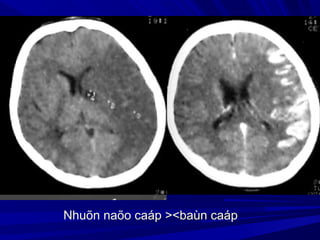

Nhuõn naõo caáp ><baùn caáp

Fogging effect: Hiện tượng đồng đậm độFogging effect: Hiện tượng đồng đậm độ

vùng nhồi máu ở ngày 14-21 do tăng thựcvùng nhồi máu ở ngày 14-21 do tăng thực

bào hoặc xuất huyết vi thể, khi đó vùngbào hoặc xuất huyết vi thể, khi đó vùng

nhồi máu rất khó nhận thấy.nhồi máu rất khó nhận thấy.

Fogging EffectFogging Effect

24 giờ 11 ngày 4 tháng